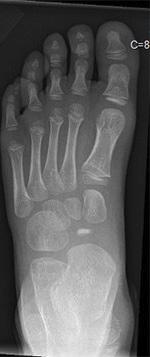

43 Riksfot – fot- och fotledskirurgi